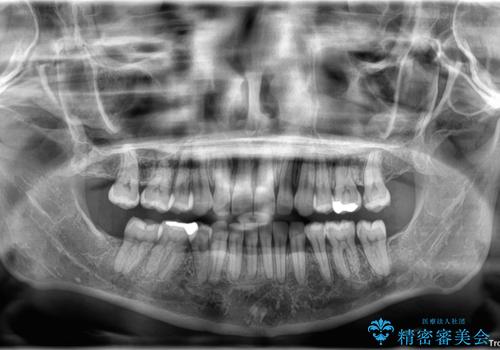

- 下顎前歯部には叢生が認められ、口を自然に閉じにくい状態でした。また、噛み合わせが深い「ディープバイト」の状態で、見た目だけでなく将来的な奥歯への負担も懸念されました。

口元の突出感を改善するため、上下左右の小臼歯4本を抜歯する矯正治療を計画しました。